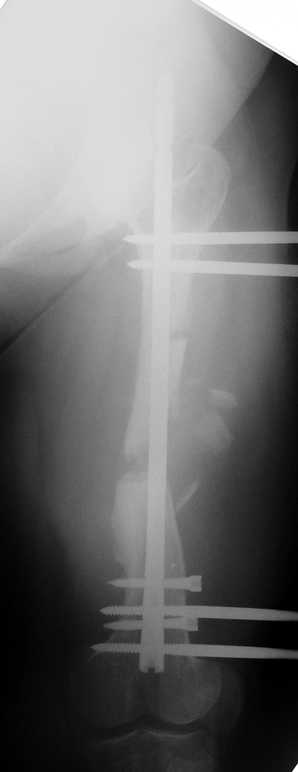

3. POSTTRAUMATIC LOWER LIMB SHORTNESS (MALUNION)

This type of shortness occurs after a fracture heals in a shortened position. Most cases are seen in adults and can be treated with one lengthening operation. Additional deformities can be corrected simultaneously. Most of these cases can be treated with lengthening over nail or just corrections and intramedullary nailing.